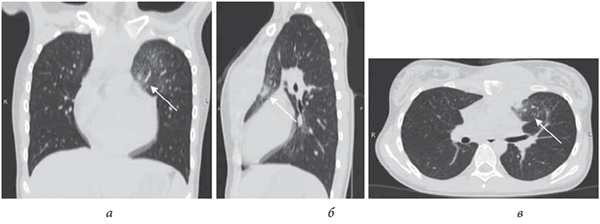

Больная Г., 12 лет, поступила в клинику с жалобами на опухолевидное образование с гнойным отделяемым в области грудины. Из анамнеза известно, что образование появилось шесть месяцев назад, после травмы (падение с высоты собственного роста на спину), не сопровождалось местными воспалительными явлениями. При обращении за медицинской помощью ситуация расценена как ушиб грудной клетки, проведено местное лечение с использованием физиотерапии (УВЧ № 7), мазей с противовоспалительными препаратами (НПВП, бепантен, акридерм) без положительной динамики. В дальнейшем появились периодические подъемы температуры, гиперемия, локальный отек тканей в области образования. При повторном обращении к хирургу диагностирован «абсцесс грудной клетки», который вскрыт и дренирован, при этом, по описанию, получен гной и патологические массы, расцененные как «казеозные». По результату цитологического исследования мазка кислотоустойчивых бактерий (КУБ) не выявлено. Проведен курс неспецифической антибактериальной терапии (цефтриаксон, метрагил, амикацин, гентамицин), на фоне которой сформировался свищ со скудным слизистым отделяемым. Выполнена компьютерная томография органов грудной клетки, при которой обнаружены деструкция в рукоятке и теле грудины с парастернальным жидкостным компонентом (рис. 2) и инфильтративные изменения в третьем сегменте левого легкого (рис. 3).

Рис. 2. Больная Г., 12 лет. КТ-срезы грудной клетки (костный режим): а —фронтальный; б — аксиальный; в — сагиттальный. Стрелкой указана область деструкции грудины

Рис. 3. Больная Г., 12 лет. Компьютерные томограммы грудной клетки (легочной режим): а — фронтальный срез; б — сагиттальный срез; в — аксиальный срез. Стрелкой указана зона инфильтративных изменений в S3-сегменте слева